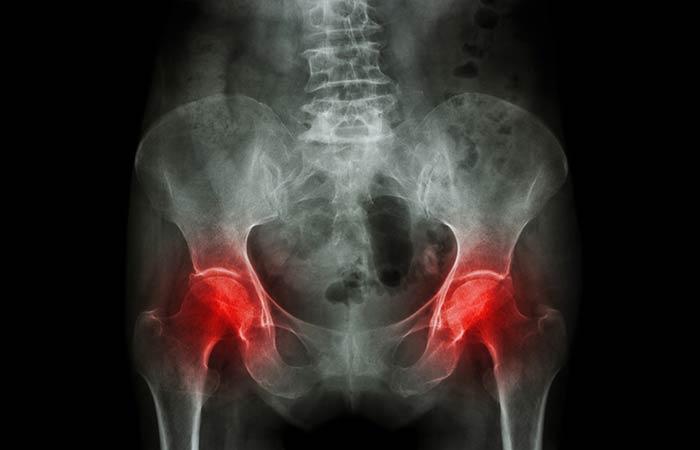

5. Pelvic Pain

Every woman is familiar with the location of this pain, as she suffers from cramps during her monthly period. But if she is pregnant, this may indicate the possibility of a miscarriage. This pain could also be due to abnormalities in the uterus or ovaries such as fibroids, abnormal tissue growth, and cysts, which cause pelvic pain. But this pain can occur irrespective of gender if it is caused by a hernia, colon cancer, kidney stone or Crohn’s disease, which is an inflammatory bowel disease.